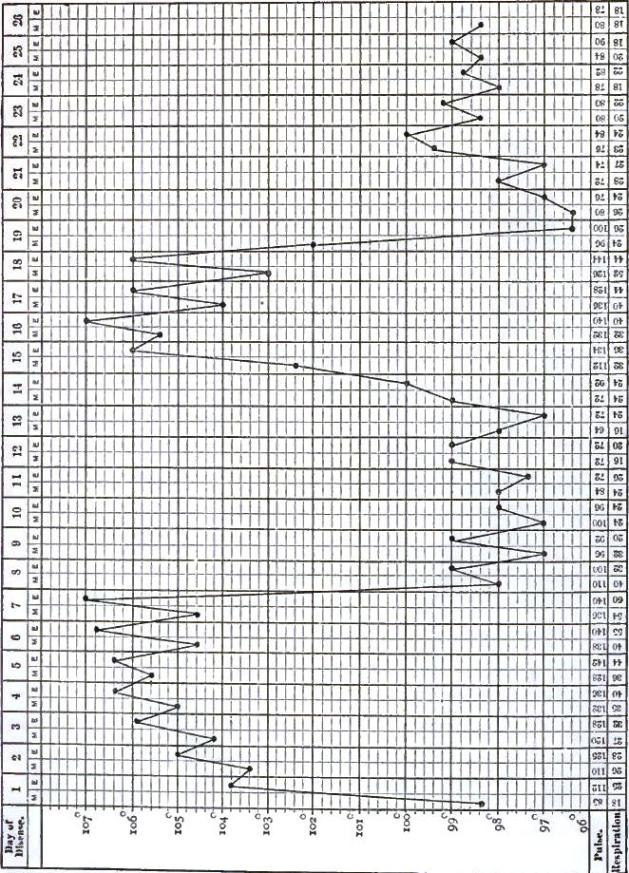

| 18. | TEMPERATURE CHART OF TYPHOID FEVER.—ABORTIVE ATTACK, FOLLOWED BY TYPICAL ATTACK |

| 19. | SPIRILLUM FROM THE BLOOD IN A CASE OF RELAPSING FEVER |

| 20. | TEMPERATURE CHART OF TYPICAL CASE OF RELAPSING FEVER, WITH THREE RELAPSES TERMINATING IN RECOVERY |

| 21. | TEMPERATURE CHART OF TYPICAL CASE OF RELAPSING FEVER, TERMINATING IN RECOVERY |

| 22. | TEMPERATURE CHART FROM A CASE OF THE BILIOUS TYPHOID OR GRAVE SUBINTRANT FORM OF RELAPSING FEVER |

| 23. | TEMPERATURE CHART SHOWING THE LAPSE OF A REMITTENT FEVER INTO AN INTERMITTENT |

| 24. | CHARTS SHOWING THE TEMPERATURE CURVE IN TYPHO-MALARIAL FEVER: PART I., SHOWING PREDOMINANCE OF TYPHOIDAL ELEMENT; PART II., SHOWING PREDOMINANCE OF MALARIAL ELEMENT |